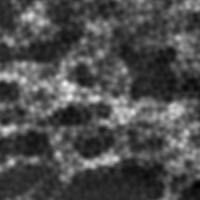

For completeness, we also show the intermediate outputs of the algorithm, using the same parameters as in section 3.3. The first of the generated images (panel b) is the output of the network after the pre-training phase using pixel-wise loss only. The second (panel c) is after a a full training phase using pixel-wise and perceptual loss (no adversarial part) and the last one (panel d) is with the full loss. The results are shown for the same cell sample on three different channels.

(a) Bicubic

(20.35 / 0.41)

Refer to caption

(b) Pixel-wise loss

(25.44 / 0.77)

(c) Perceptual loss

(24.64 / 0.71)

(d) GAN loss

(24.96 / 0.74)

(e) SIM

a

Figure 9: Results of our algorithm on an unseen image in the W2S dataset [13], first channel. (a) Low resolution widefield image upscaled using bicubic interpolation. (b) Output of our model after the first training phase using pixel-wise loss only. (c) Output of our model after the full training using pixel-wise and perceptual loss.(d) Output of our model in our final solution using full loss. (e) Corresponding image obtained using a SIM process. PSNR and SSIM values are shown in parenthesis.

We can see in Figures 9,10,11 that the pre-training phase (panel b) does already apply a significant denoising to the image. However, as was shown in ESRGAN [10], the results obtained with pixel-wise approaches are over-smoothed, as can be seen in the image, that is still blurry. The perceptual approaches with and without the adversarial part (panels d and c) are visually closer to the ground-truth. One can observe that the image without the GAN loss (panel c) is even a bit sharper. This result is also coherent with the observations in ESRGAN [10], that stated that approaches with a strong focus on perceptual loss tend to yield sharper results, but can be accompanied by unpleasant artifacts. This is the reason we prefer the approach with adversarial loss, that is arguably more resistant to such artifacts. We can also observe that neither the PSNR or the SSIM correlate with perceptual quality, as both values are most of the time the highest after the pre-training phase, where the denoising is less effective than after a full training procedure.